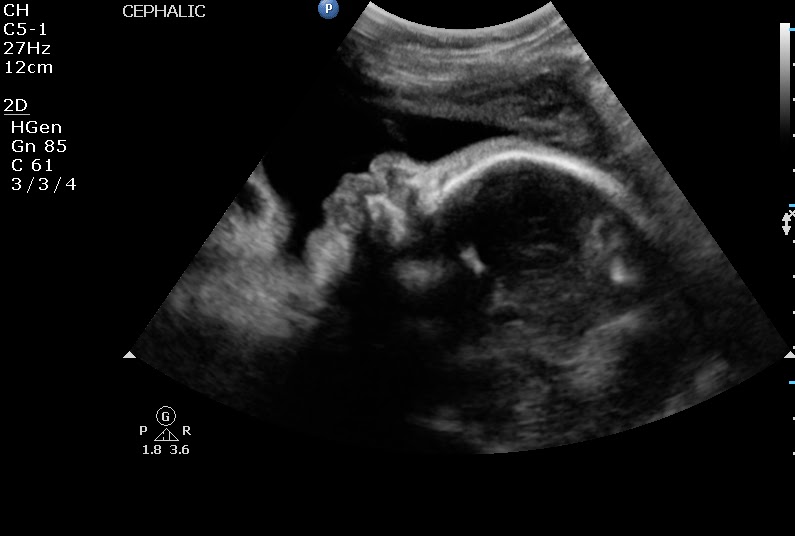

We had our second ultrasound and were able to see our beautiful baby boy again. We were hoping we would be able to get a 3D ultrasound but unfortunately they aren't able to do those in the local office. We found out that the placenta moved which was the point of having another ultrasound and what we were praying for. He was still just as active as ever and like before the ultrasound tech had a difficult time getting the pictures she needed but we were able to see much more of his face this time! His little lips look crazy in these pictures, he must have been moving them. :) I can't wait to see what he looks like, I can't really picture what a Dustin/Karissa baby looks like and am a little weirded out to see the blend. Hopefully he's a cute mix, haha!

![]() |

| Fish lips ;-) |